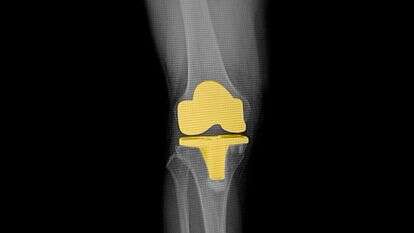

כעשרים אחוזים מהמטופלים חווים כאבי ברכיים או כאבים אחרים במשך כמה חודשים אחרי הניתוח, כאשר הם מתגברים אחרי פעילות מאומצת. בכל השנים האחרונות העולם הרפואי פועל בשביל למזער את הכמות של הכאב אשר אותה חווים אחרי הניתוח הזה, דרך כמה שיטות של ניתוח שהן חדשניות יותר, וטיפול רפואי שהוא כמובן מותאם אישית. השיקום מהניתוח להחלפת ברך מתחיל כמובן, כבר מהיום הראשון. במהלך הניתוח, כנראה שאתם תהיו תחת הרדמה כללית ואתם תישנו במהלכו של כל הניתוח, או שאתם תהיו תחת הרדמה שהיא מקומית בלבד, ששם אתם כמובן תהיו מורדמים מאזור האגן ולמטה, אבל לא תישנו. ההרדמה המקומית דומה מאוד לאפידורל אשר ניתן במהלך הלידות. לאחר שההשפעה של חומרי ההרדמה תפוג, הצוות הרפואי יספק לכם מספר משככי כאבים דרך הפה, או פשוט אל הוריד דרך עירוי.

ניתוח של החלפת מפרק ברך והתהליך של השיקום וכל ההחלמה אחרי הניתוח, מומלץ וחשוב מאוד שיתבצעו תחת ליווי אישי של אורתופד שהוא מומחה ברכיים, וזאת בשביל צרכי התכנון המיטבי של הניתוח, וגם בשביל צרכי ההיערכות המיטבית של כל תקופת השיקום, בהתאמה מלאה אל המצב הבריאותי של המטופל והגיל שלו. בדיקות שונות אשר מטרתן מעקב לאחר המצב של המטופל בזמן השיקום וההחלמה, עוזרים גם הם לבנייה של תכנית שיקומית מיטבית ואיכותית של טיפולי פיזיותרפיה, כשתכנית הטיפול וההיקף של השעות של התרגול מותאמים אל הממצאים של בדיקות המעקב.